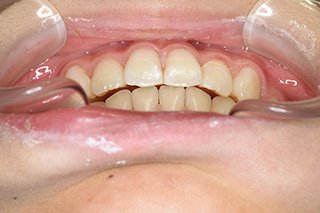

顎顔面矯正症例 11歳女児 Case

| 主訴 | 永久歯が変な所からはえてきている|顔貌 | |

|---|---|---|

| 施術内容 | 矯正1期治療 | |

| 治癒期間 | 1年5ヶ月間 | |

| 費用 | 459,200円(税込) | |

| リスク・ 副作用 | 痛みを伴う | |